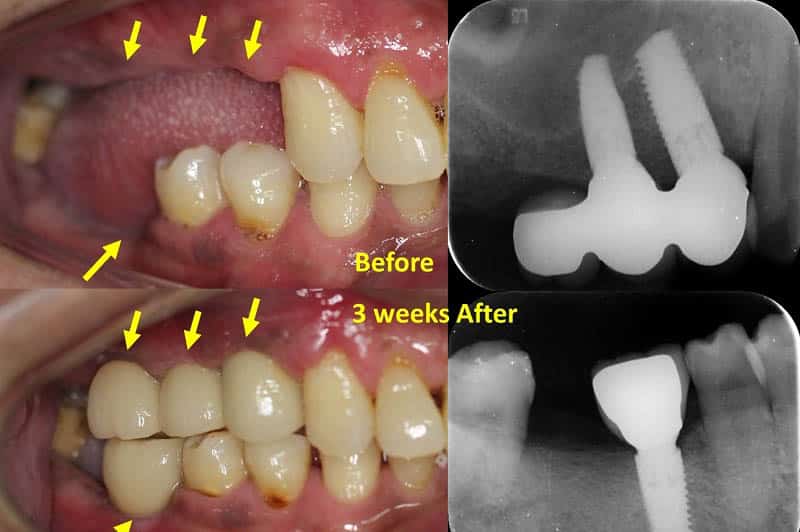

Cấy ghép Implant tức thì sau khi nhổ răng

Sau khi nhổ, chân răng được lấy ra khỏi xương hàm và để lại 1 lỗ hổng. Bác sĩ sẽ khoan tạo hình và đặt trụ Implant ngay tại vị trí răng vừa nhổ.

- Ưu điểm: tiết kiệm được rất nhiều chi phí, thời gian và giảm đau đớn vì chỉ phải phẫu thuật 1 lần duy nhất đồng thời giữ cho cơ mặt không bị ảnh hưởng. Việc thay thế chân răng nhân tạo thay thế cho chân răng nhổ ra sẽ tránh được tình trạng tiêu xương, giảm thời gian điều trị và sang chấn mô. Ngoài ra, việc trồng răng Implant ngay sau khi nhổ sẽ giúp bệnh nhân giữ được nét tự nhiên và mang lại sự hài hòa gần như tuyệt đối với răng thật.

Sau khi nhổ răng bao lâu thì trồng Implant

- Nhược điểm: do kích thước của răng thật và răng Implant có sự khác nhau nên bệnh nhân sẽ phải ghép thêm xương và đặt màng collagen để hỗ trợ lành thương nhanh chóng. Ngoài ra, sự ổn định ban đầu của răng Implant cũng kém hơn và có nhiều biến chứng hơn so với khi đợi lành thương hẳn mới cấy ghép. Bác sĩ sẽ rất khó tiên lượng được sự tiêu xương, tiêu mô mềm dẫn đến tình trạng bị tụt lợi sau khi cấy ghép. Vì vậy, chỉ nên thực hiện trồng răng Implant tức thì ngay sau khi nhổ khi chân răng nhổ không quá lớn và xương còn lại vẫn đủ nhiều để đảm bảo sự siết chặt Implant trong xương hàm.